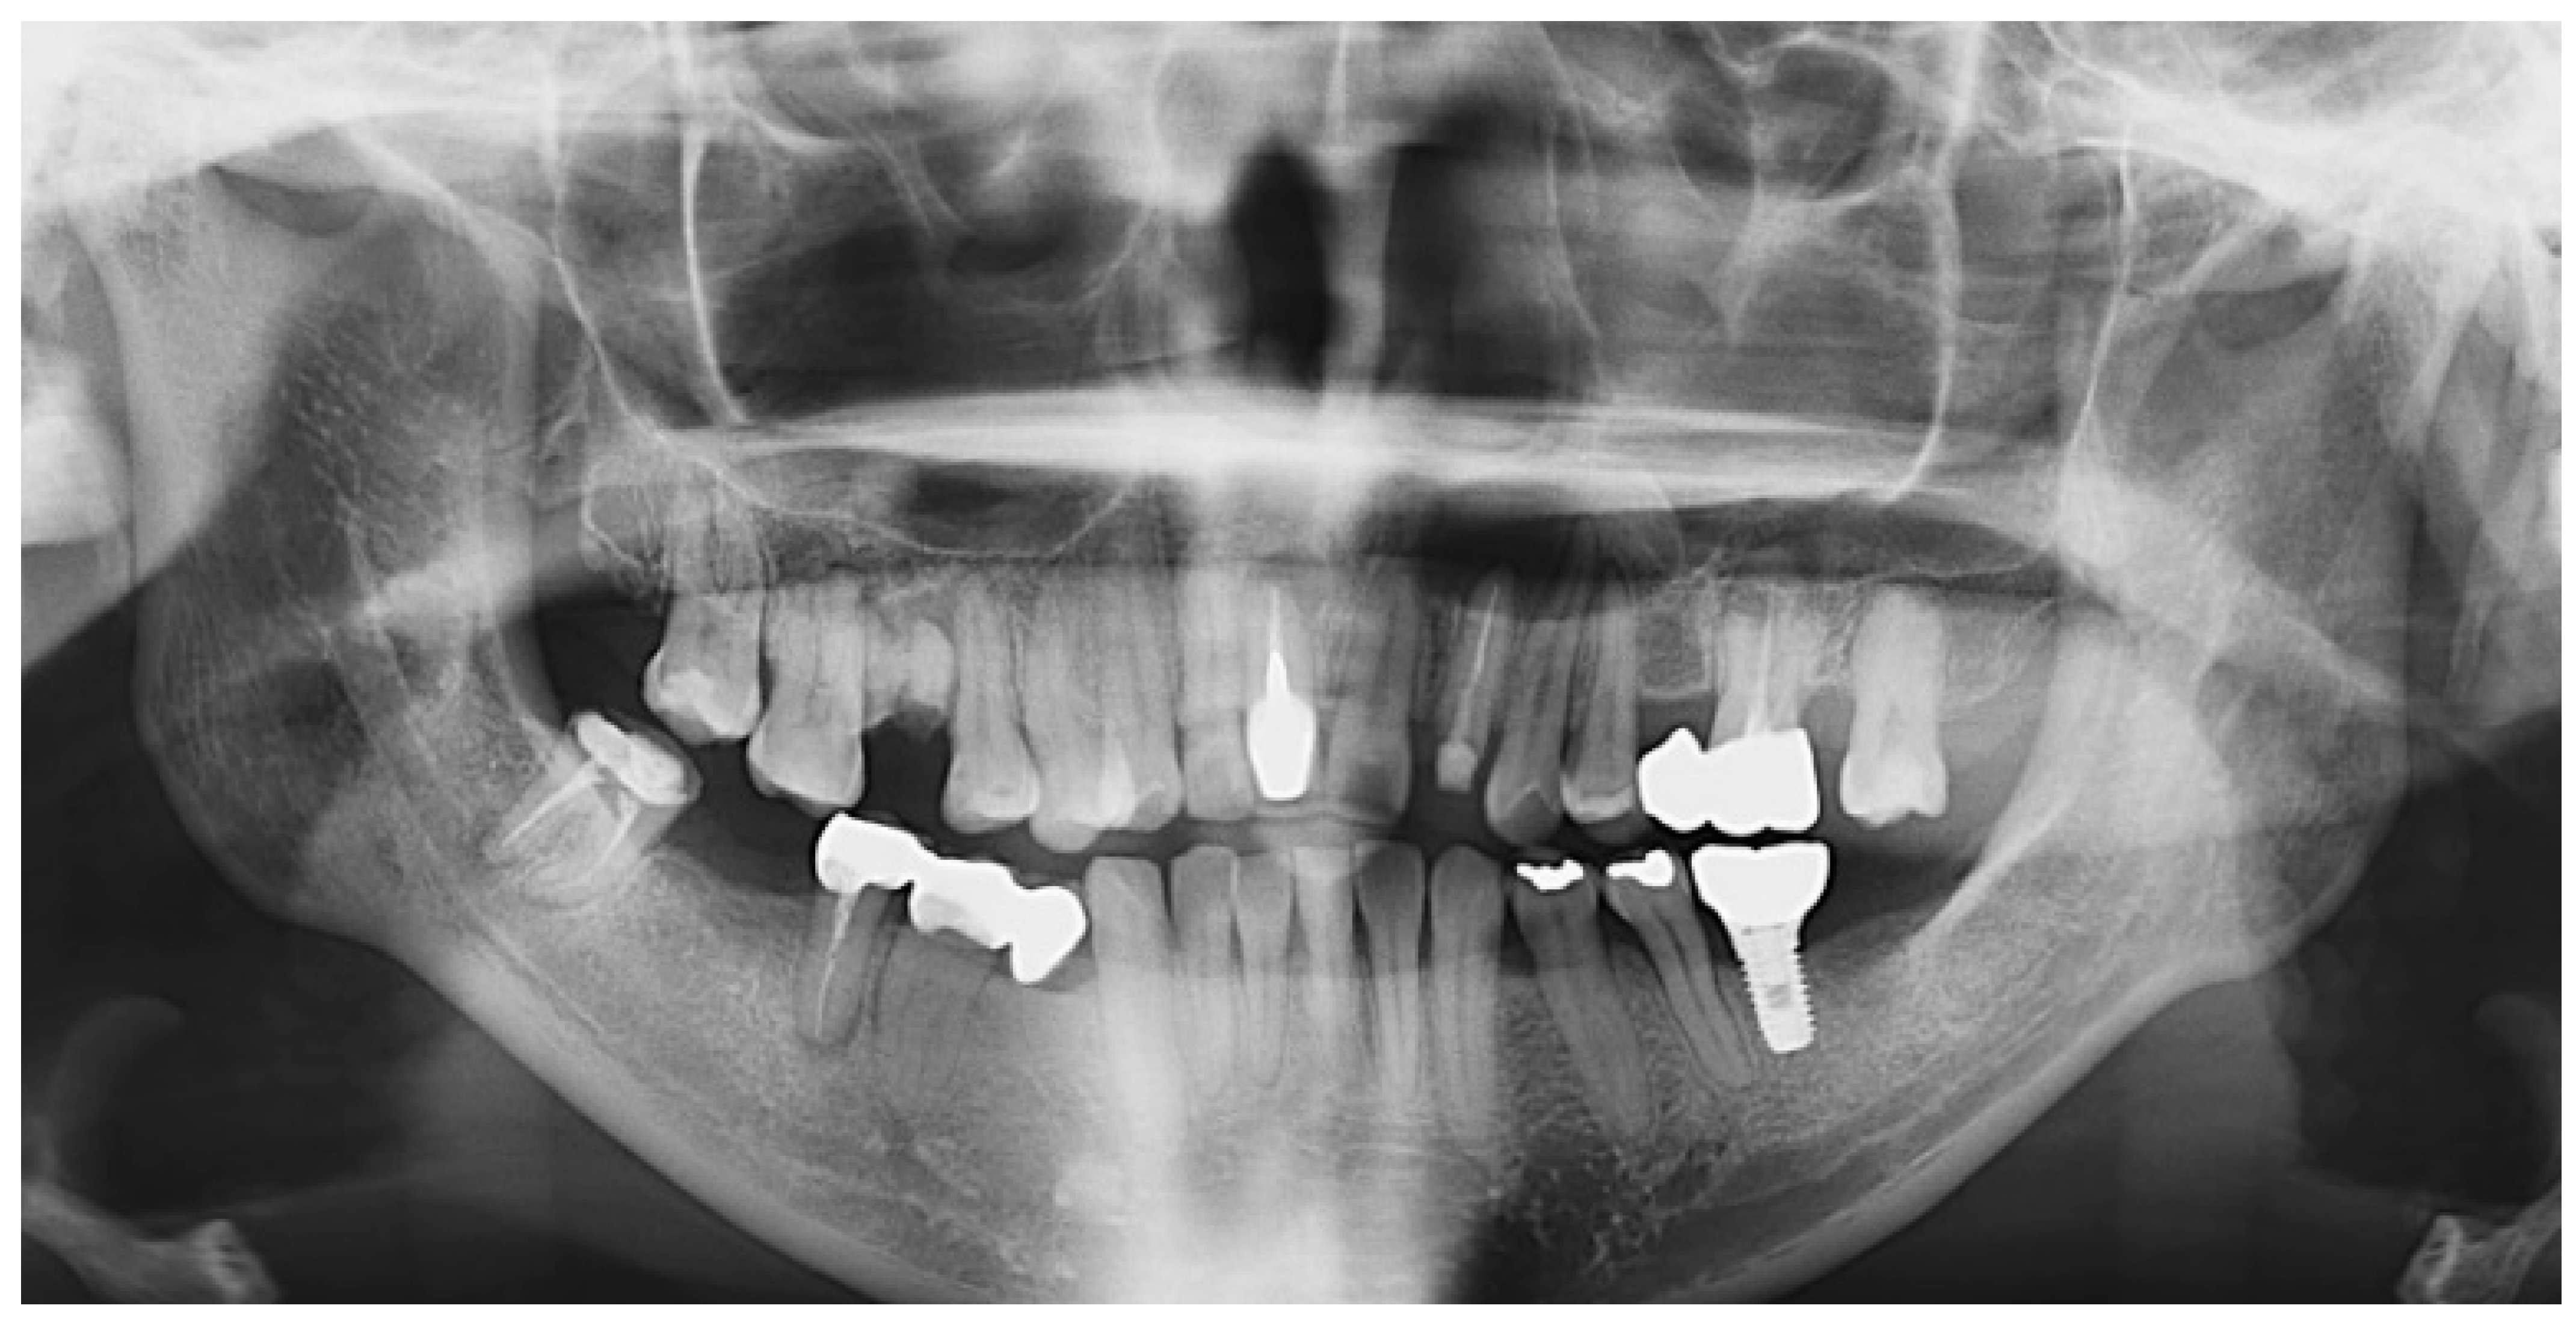

Panoramic XRay Missouri Upper Lower Jaw Xrays St. Peters & Wentzville Jaw Cyst X Ray Cystic should not be confused with lytic as solid radiolucent lesions can also appear lytic (see: A series of 3d images that show the. Radiolucent lesions of the jaw). An odontogenic cyst associated with the apex of a tooth with a crown, thus a diseased tooth, is consistent with a periapical radicular cyst. Most cysts or tumors that develop in. Jaw Cyst X Ray.